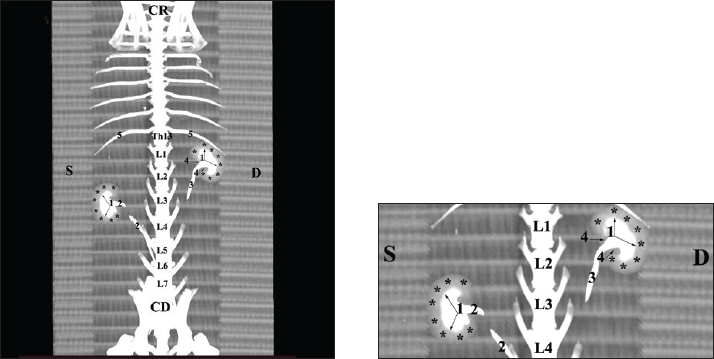

Fig. 19. Post-contrast computed tomography (CT) anatomical scan of the regio-abdominis cranialis at the L5 level: (1) Ren sinister; (2) adipose collections; (3) cecum; (4) colon ascendens; (5) colon transversum; (6) colon descendens; (7) mesenterium; (8) ureter; (9) aorta abdominalis; (10) v. cava caudalis; (*) cortex renalis; (**) capsula adiposa. Retrospective reconstructionsThe retrospective reconstruction in the Bones and Skin 1 and Bones and Skin 3 modes provided information about the anatomical features of both kidneys, including surface relief and renal pyramids. The two kidneys were multipapillar organs with 6–8 pyramids; their tips were fused into a single crista renalis, directed toward the renal pelvis. Dorsally and ventrally, the renal pelvis became wider to form recessus renalis, аnd its terminal part continued toward the ureter. The cortex renis and medulla renis were distinct soft tissue findings, and the boundary between the capsula fibrosa and capsula adiposa was clearly defined (Figs. 20 and 21).

Fig. 20. Retrospective reconstruction of computed tomography (CT) data in Bones and Skin 1 mode in a rabbit: (1) Crista renalis; (2) left ureter; (3) right ureter; (4) recessus renalis; (*) papilla renalis; (5) XIII rib.

Fig. 21. Retrospective reconstruction of computed tomography data in Bones and Skin 3 mode in a rabbit. (1) XIII h rib; (2) extremitas cranialis; (3) extremitas caudalis; (4) capsula adiposa; (5) pelvis renalis (right kidney); (6) right ureter (pars abdominalis); (7) pars descendens of the duodenum; (8) pelvis renalis (left kidney); (9) left ureter (pars abdominalis); (10) lobus caudatus (proc. caudatus); (11) pars ascendens of the duodenum. Retrospective reconstruction in the Angio–Right and Left mode (right and left sides) yielded information about the localization of both kidneys in the RA. The right kidney was located in the region abdominis cranialis and region abdominis media, between Th13 (L1) and L2–L3, whereas the left kidney was located between L2 (L3) and L4 (L5) (Figs. 22 and 23).

Fig. 22. Retrospective reconstruction of computed tomography (CT) data in Angio–Right and Left 1 mode in a rabbit (right side). (1) 13th rib; (2) extremitas cranialis; (3) extremitas caudalis; (4) right ureter (pars abdominalis); (5) right ureter (pars pelvina); (6) colon; (7) left ureter (pars abdominalis); (8) left ureter (pars pelvina); (9) lobus caudatus (proc. caudatus); (10) pars descendens of the duodenum; (11) ileum; (12) colon ascendens; (13) cecum; (*) v. cava caudalis; (**) aorta abdominalis.

Fig. 23. Retrospective reconstruction of computed tomography data in Angio–Right and Left 1 mode in a rabbit (left side). (1) Extremitas cranialis; (2) Extremitas caudalis; (3) Left ureter (pars abdominalis); (4) Left ureter (pars pelvina); (5) Vesica urinaria; (6) Cecum; (7) Colon ascendens; (*) Aorta abdominalis. Statistical and metric analysesSoft tissue density was measured on pre-contrast CT scans to obtain objective data. The density of the right kidney was 40.28 ± 6.6 HU, and that of the left kidney was 43.36 ± 5.2 HU (Table 1). Table 1. CT values of rabbit kidneys in the HU.